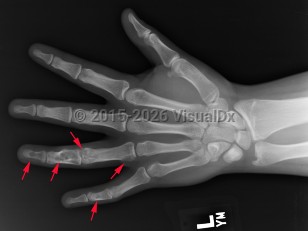

Ollier disease and Maffucci syndrome are nonhereditary conditions that present as multiple enchondromas. Ollier disease involves multiple asymmetric enchondromas of the digits. It is most commonly seen in childhood. These slow-growing tumors usually stop growing after puberty, but masses can create deformity and limb asymmetry. Pathologic fractures may be seen. Ollier disease has a 15%-20% risk for secondary chondrosarcoma.

Prevalence: Enchondroma is a latent lesion that comprises 15%-25% of cartilage tumors. It is the most common hand tumor, accounting for 90% of cases. Enchondroma usually presents in the third and fourth decades of life and occurs equally between both sexes.

Pathophysiology: Enchondroma pathophysiology is believed to involve incomplete endochondral ossification in which physeal remnants become entrapped in the medullary cavity of the metaphysis and proliferate. In the hand, enchondromas are typically diagnosed after a pathologic fracture. Elsewhere, they are typically an asymptomatic incidental finding on x-ray or advanced imaging performed for other reasons. Pain is usually due to a nearby abnormality rather than the tumor itself.